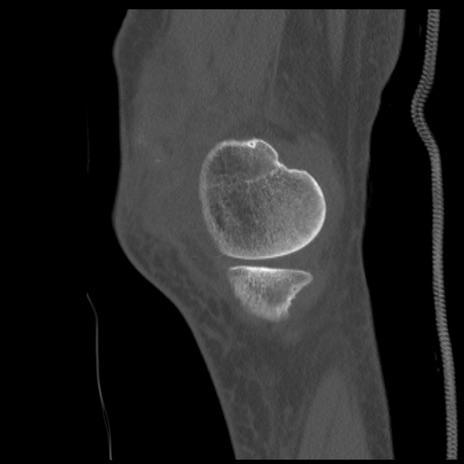

症例28 右膝関節CT(矢状断像)

右膝関節CT